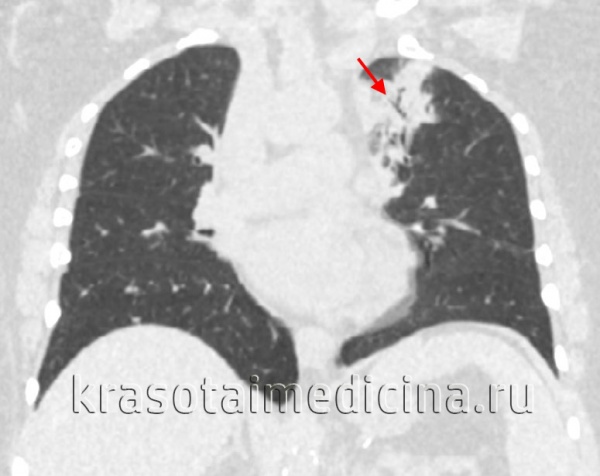

Спиральная КТ и МРТ легких применяются при дифференциации диагноза. При диагностике бактериальной пневмонии требуется исключить инфильтративный туберкулез, рак легкого, инфаркт легкого, эозинофильный инфильтрат, застойную сердечную недостаточность, ателектаз легкого.

КТ ОГК. Множественные обширные участки снижения пневматизации по типу консолидации в нижних долях обоих легких.